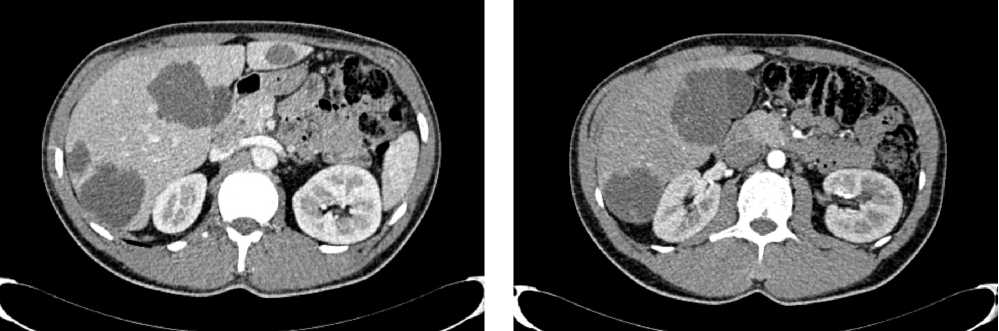

По решению онкологического консилиума пациенту начат ПХТ 1 линии в режиме FOLFOX + бевацизумаб. С 02.09.2022 проведено 3 цикла ПХТ 1 линии, по результатам контрольных обследований зарегистрировано прогрессирование процесса за счет роста образований печени до 64 × 46 мм и появления линзовидного образования между передней поверхностью прямой кишки и задней поверхностью предстательной железы размерами 47 × 15 × 25 мм (рис. 7, 8).

Рис. 7. Результаты компьютерной томографии органов брюшной полости у пациента 37 лет с диагнозом метастатический колоректальный рак с признаками микросателлитной нестабильности (октябрь 2022 г., после 3-х циклов FOLFOX + бевацизумаб)

Fig. 7. Results of abdominal CT scan in a 37-year-old patient diagnosed with metastatic MSI-H colorectal cancer (October 2022, after 3 cycles of FOLFOX + bevacizumab)

Рис. 8. Результаты магнитно-резонансной томографии органов брюшной полости у пациента 37 лет с диагнозом метастатический колоректальный рак с признаками микросателлитной нестабильности (октябрь 2022 г., после 3-х циклов FOLFOX + бевацизумаб)

Fig. 8. Results of abdominal MRI in a 37-year-old patient diagnosed with metastatic MSI-H colorectal cancer (October 2022, after 3 cycles of FOLFOX + bevacizumab)